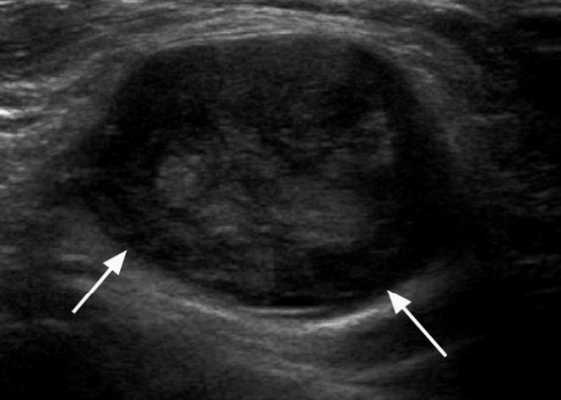

Изменения лимфоузлов на УЗИ при злокачественных новообразованиях

В ходе УЗИ ЛУ можно заподозрить наличие у исследуемого опухоли с агрессивным течением. Выявить прорастание последней или метастазы в лимфоузлы с помощью пальпации невозможно. Благодаря неинвазивности, высокой информативности и доступности, ультразвуковое сканирование является методом скрининга как при первичной диагностике злокачественных процессов в крови, лимфе, внутренних органах, так и у больных после оперативного лечения и/или химиотерапии.

УЗИ с допплерографией у пациентов онкологического профиля показывает следующие нарушения в строении ЛУ:

- увеличение в размерах - обычно до 6-6,5 см;

- шарообразную деформацию или неправильные контуры;

- спаянность в виде конгломератов;

- отсутствие дифференциации на кору и ворота;

- неоднородность структуры с зонами повышенной и пониженной эхогенности;

- жидкостные включения и кальцинаты;

- усиленный кровоток и образование новых сосудов (ангиогенез).

Указанные изменения на снимках чаще обнаруживают при лимфоме.